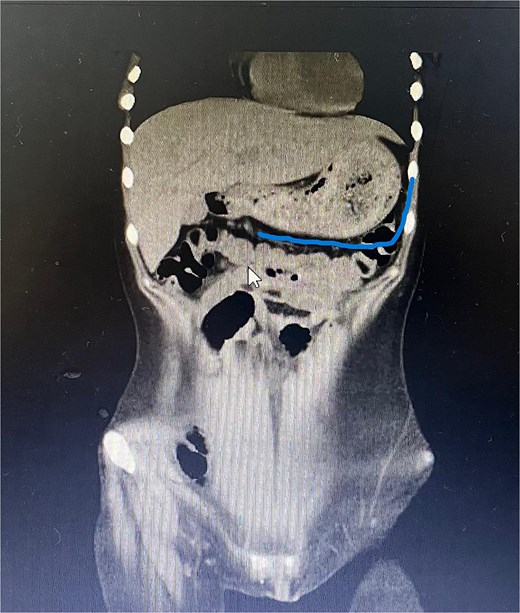

Twelve hours later, she was evaluated by the new emergency surgery team, who found a complete upper obstruction with a foreign body occupying the lower esophagus, the entire stomach, and the entire duodenum (Figs 1–3). A diagnostic laparoscopy (Fig. 10) with gastrotomy was performed (Figs 4 and 5), including foreign body removal (Figs 6 and 7), gastric repair (Fig. 8), and placement of a tubular drain. The findings revealed a large foreign body containing a significant amount of malodorous hair, measuring 30 cm long and 12 cm wide (Fig. 9). Large gauze pads were placed around the stomach to prevent contamination, and the bezoar was removed first through the duodenal area, as this was the area of smallest diameter and least compression. The gastric and esophageal portions were then removed. The foreign body was extracted transumbilically through a small 6 cm incision, protecting the abdominal wall with an isolation device. Gastric repair was performed using a 3–0 continuous suture polydioxanone (PDS) in a single layer. The cavity was irrigated with 3 l of saline solution. The operation was 2 h. Postoperative management included a nasogastric tube on gravity drainage, intravenous piperacillin/tazobactam 4.5 g every 6 h, intravenous tramadol 100 mg every 8 h for analgesia, and intravenous dimenhydrinate 50 mg every 8 h. The patient progressed favorably, with oral intake initiated on postoperative day 4. The tubular drain was removed on day 5 with minimal serous output. Psychiatry discovered that the patient had been diagnosed with trichotillomania in 2014 but refused pharmacological treatment. The patient confirmed that she has suffered from trichophagia since the age of 14. Pharmacological treatment with psychotropic medications and psychological support was initiated. On day 7, the patient was on a soft diet, without a nasogastric tube, with a white blood cell count of 10 740 cells/μl and 0% band neutrophils. Treatment with clomipramine was initiated. She was discharged that day and evaluated 7 days later with no problems.

Axial CT image showing the foreign body completely occupying the gastric lumen.